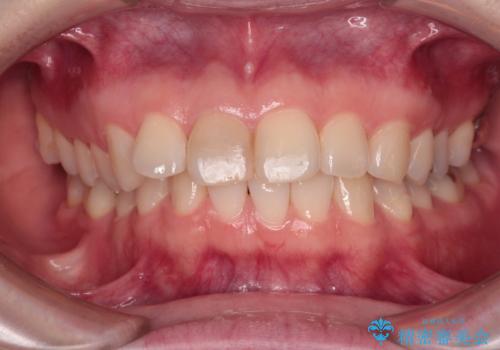

- 事故でぶつけて神経を取り除いた歯が変色したとのことで来院された患者様です。

処置直後は欠けた部分を詰めた材料で見た目に問題なかったそうですが、年々変色してきて、かなり目立つようになっていました。

根管治療された状態に大きな問題はなかったため、土台を植立し、オールセラミッククラウンにて補綴治療を行うこととしました。